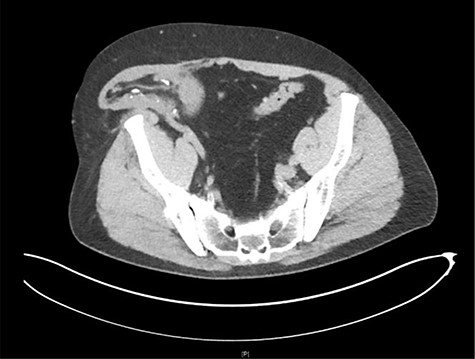

His workup was included but not limited to basic labs (CBC, CMP and UA), a renal transplant ultrasound, and a CT of the abdomen and pelvis. The CT scan revealed herniation of the right-sided donor kidney through an incisional hernia (Figs 1 and 2).

Sagittal view CT: herniation of the transplanted kidney through the right abdominal wall.